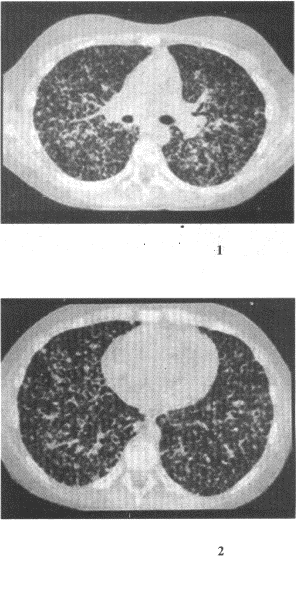

患者女,19岁,低热,盗汗,乏力,咳嗽1个月余。![]() |

| 15.CT检查如图,最可能的诊断是 |

| 正确答案:15.C;16.A;17.D 解题思路:CT上两肺呈弥漫性粟粒性结节状密度增高影,有典型的三均匀征象,即分布、大小、密度均匀,并有结核中毒症状,可诊断为粟粒型肺结核。 |